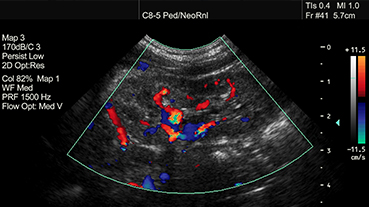

At the Children's Hospital of New York, our pediatric nephrologists from Columbia and Weill Cornell Medicine provide compassionate care for newborns to young adults with acute and chronic kidney disease. They remain on the forefront of discoveries that advance prevention, diagnosis, and treatment of these conditions, including renal replacement therapy and transplant for end-stage renal disease.

Pediatric Nephrology